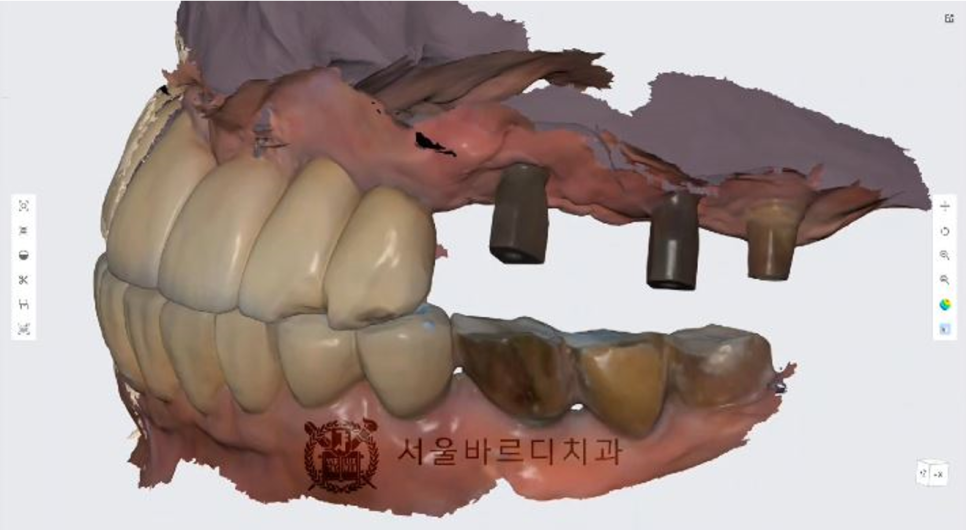

정확한 뼈 상태태를 확인하기 위해 수술전에

3D CT와 구강스캔데이터를 가지고 모의 수술을 해 본 후에

시뮬레이션 결과대로 임플란트 수술을 할 수 있게 하는

가이드 장치를 제작합니다

맞춤 장치를 제작하는 네비게이션 임플란트라고 하는데요.

더 안전하고 정확한 임플란트 수술을 위한 작업입니다.

저희 고덕치과는 스캐너 장비를 활용하여 컴퓨터 상에 정보를 담고

해당정보를 전송하여 보철물(크라운)을

제작하는 첨단 기술이 사용하고 있습니다.

이 방법은 오차 가능성을 줄여

좀더 편한 보철물을 제작하는 디지털 방식입니다.